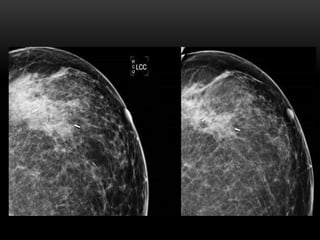

PATRÓN DEL TEJIDO GLANDULAR

1. Fibroadiposo escasa cantidad(- 25 %

glándula)

2. Fibroglandular moderada cantidad (25-50%

3. Densidad heterogénea (51-75% glándula)

4. Extremadamente denso(+ 75% glándula)